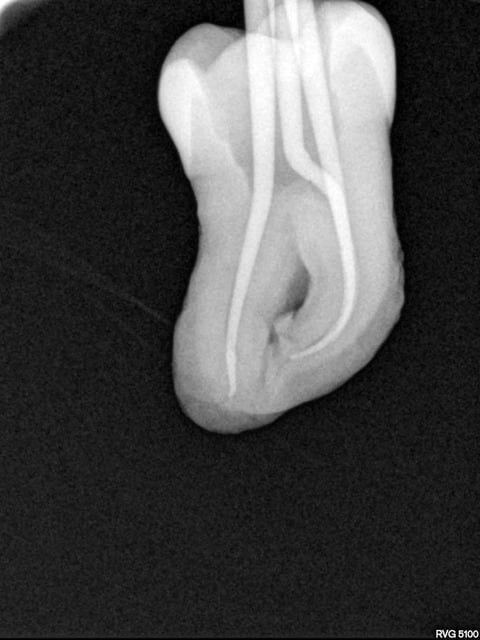

Une belle instrumentation en mésial, quelle tristesse.

Tout allait bien en progressant à patte de velours jusqu'à l'alésoir 30-4 trop fatigué apparemment (FKG Race), et j'ai donné un peu trop de force dans la progression verticale.

J'ai essayé de déloger la lime, j'ai cassé la deuxième puis la troisième.

Bon le canal est propre à défaut d'être étanche.